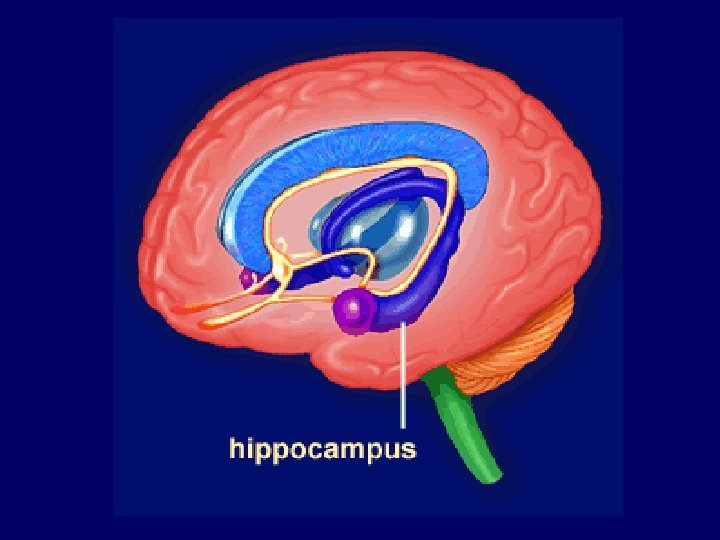

Two Limbic Circuits Anterior Thalamus Cingulate Gyrus Dorsomedial Thalamus Mamillothalamic Tract Mammilary Bodies Fornix Hippocampus Medial (Papez) Orbitofrontal Amygdalofugal pathways Uncus Amygdala Lateral

Two Limbic Circuits and the Two-system theory of amnesia Anterior Thalamus Cingulate Gyrus Dorsomedial Thalamus Mamillothalamic Tract Mammilary Bodies Orbitofrontal Amygdalofugal pathways Fornix Uncus Hippocampus Amygdala PRPH Medial (Papez) Lateral

Two Limbic Circuits and the Two-system theory of amnesia Anterior Thalamus Cingulate Gyrus Dorsomedial Thalamus Mamillothalamic Tract Mammilary Bodies Fornix Hippocampus Medial (Papez) Orbitofrontal Amygdalofugal pathways Uncus Amygdala Lateral

Two Limbic Circuits Anterior Thalamus Cingulate Gyrus Dorsomedial Thalamus Mamillothalamic Tract Mammilary Bodies Fornix Hippocampus Medial (Papez) Orbitofrontal Amygdalofugal pathways Uncus Amygdala Lateral